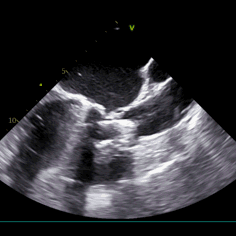

左冠灌注

术中导丝跨瓣后20mm球囊预扩,超声判断冠脉风险尚可,植入L23 VenusA Plus可回收瓣膜位置良好,用23mm球囊后扩支架下缘,微少量瓣周漏。